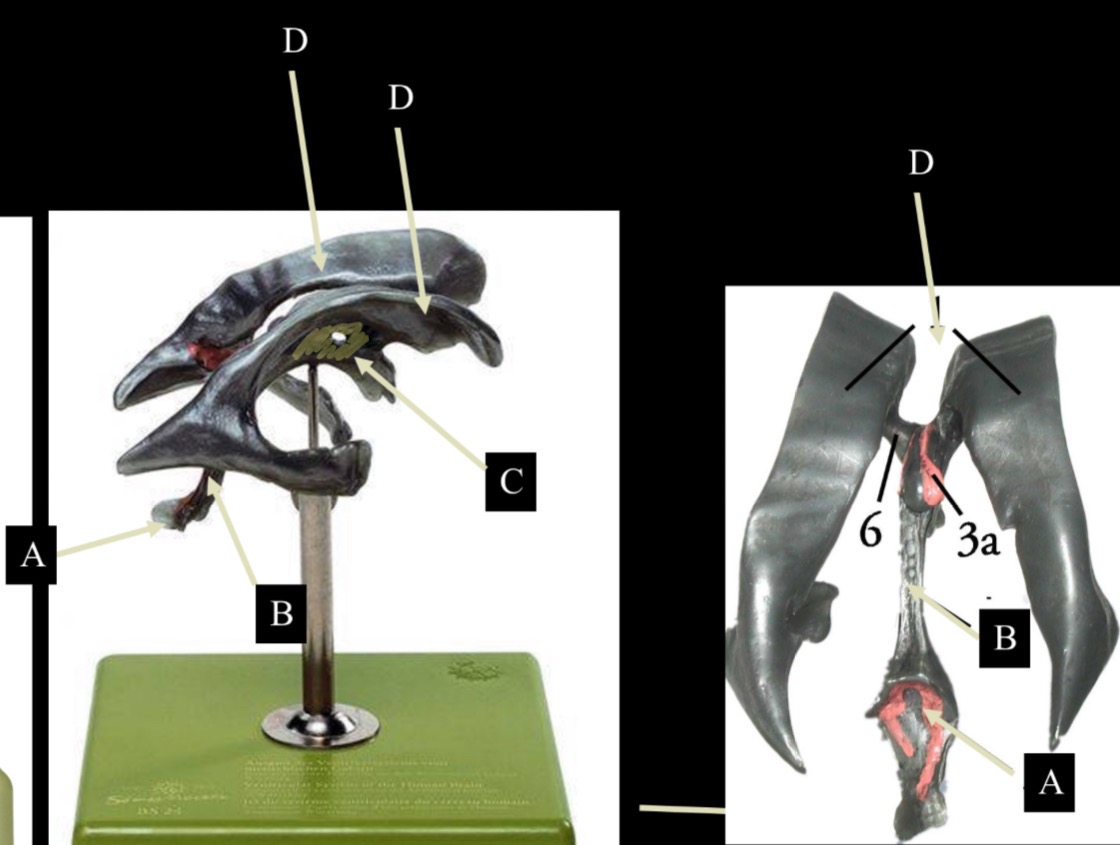

What is D?

lateral ventricle

Imagine thin membrane separating the 2 lateral ventricles

septum pellucidum

What is C?

3rd ventricle

What is B?

cerebral aqueduct

What is A?

4th ventricle

What is below A at the very end?

central canal (spinal cord)